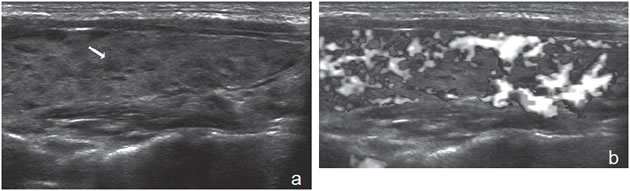

Un nódulo que tiene un componente quístico significativo, usualmente es un nódulo benigno hiperplástico, que ha acumulado abundante coloide (Figura 2a) o bien, un nódulo sólido que ha experimentado un proceso de degeneración colicuativa o hemorragia (Figura 2b). El coloide o el contenido líquido de un nódulo se ve anecogénico (negro en la imagen ecográfica) y las estructuras sólidas se ven ecogénicas (distintos tonos de grises), siendo la ecogenicidad similar al del parénquima tiroideo. En un nódulo sólido la ecoestructura y la ecogenicidad pueden ser variables. En general, la frecuencia de carcinoma es muy baja en nódulos quísticos13 y la mayoría de los carcinomas se presentan como nódulos sólidos (Figura 2c).

Figura 2. a) Quiste coloideo anecogénico y focos ecogénicos (flecha) con artefacto en cola de cometa; b) Nódulo mixto sólido-quístico (cabezas de flechas). Imagen vegetante (flecha) adherida a un tabique que se proyecta al lumen; c) Comparación entre el aspecto ecográfico de un cáncer papilar sólido (flecha abierta) y un quiste coloideo anecogénico.